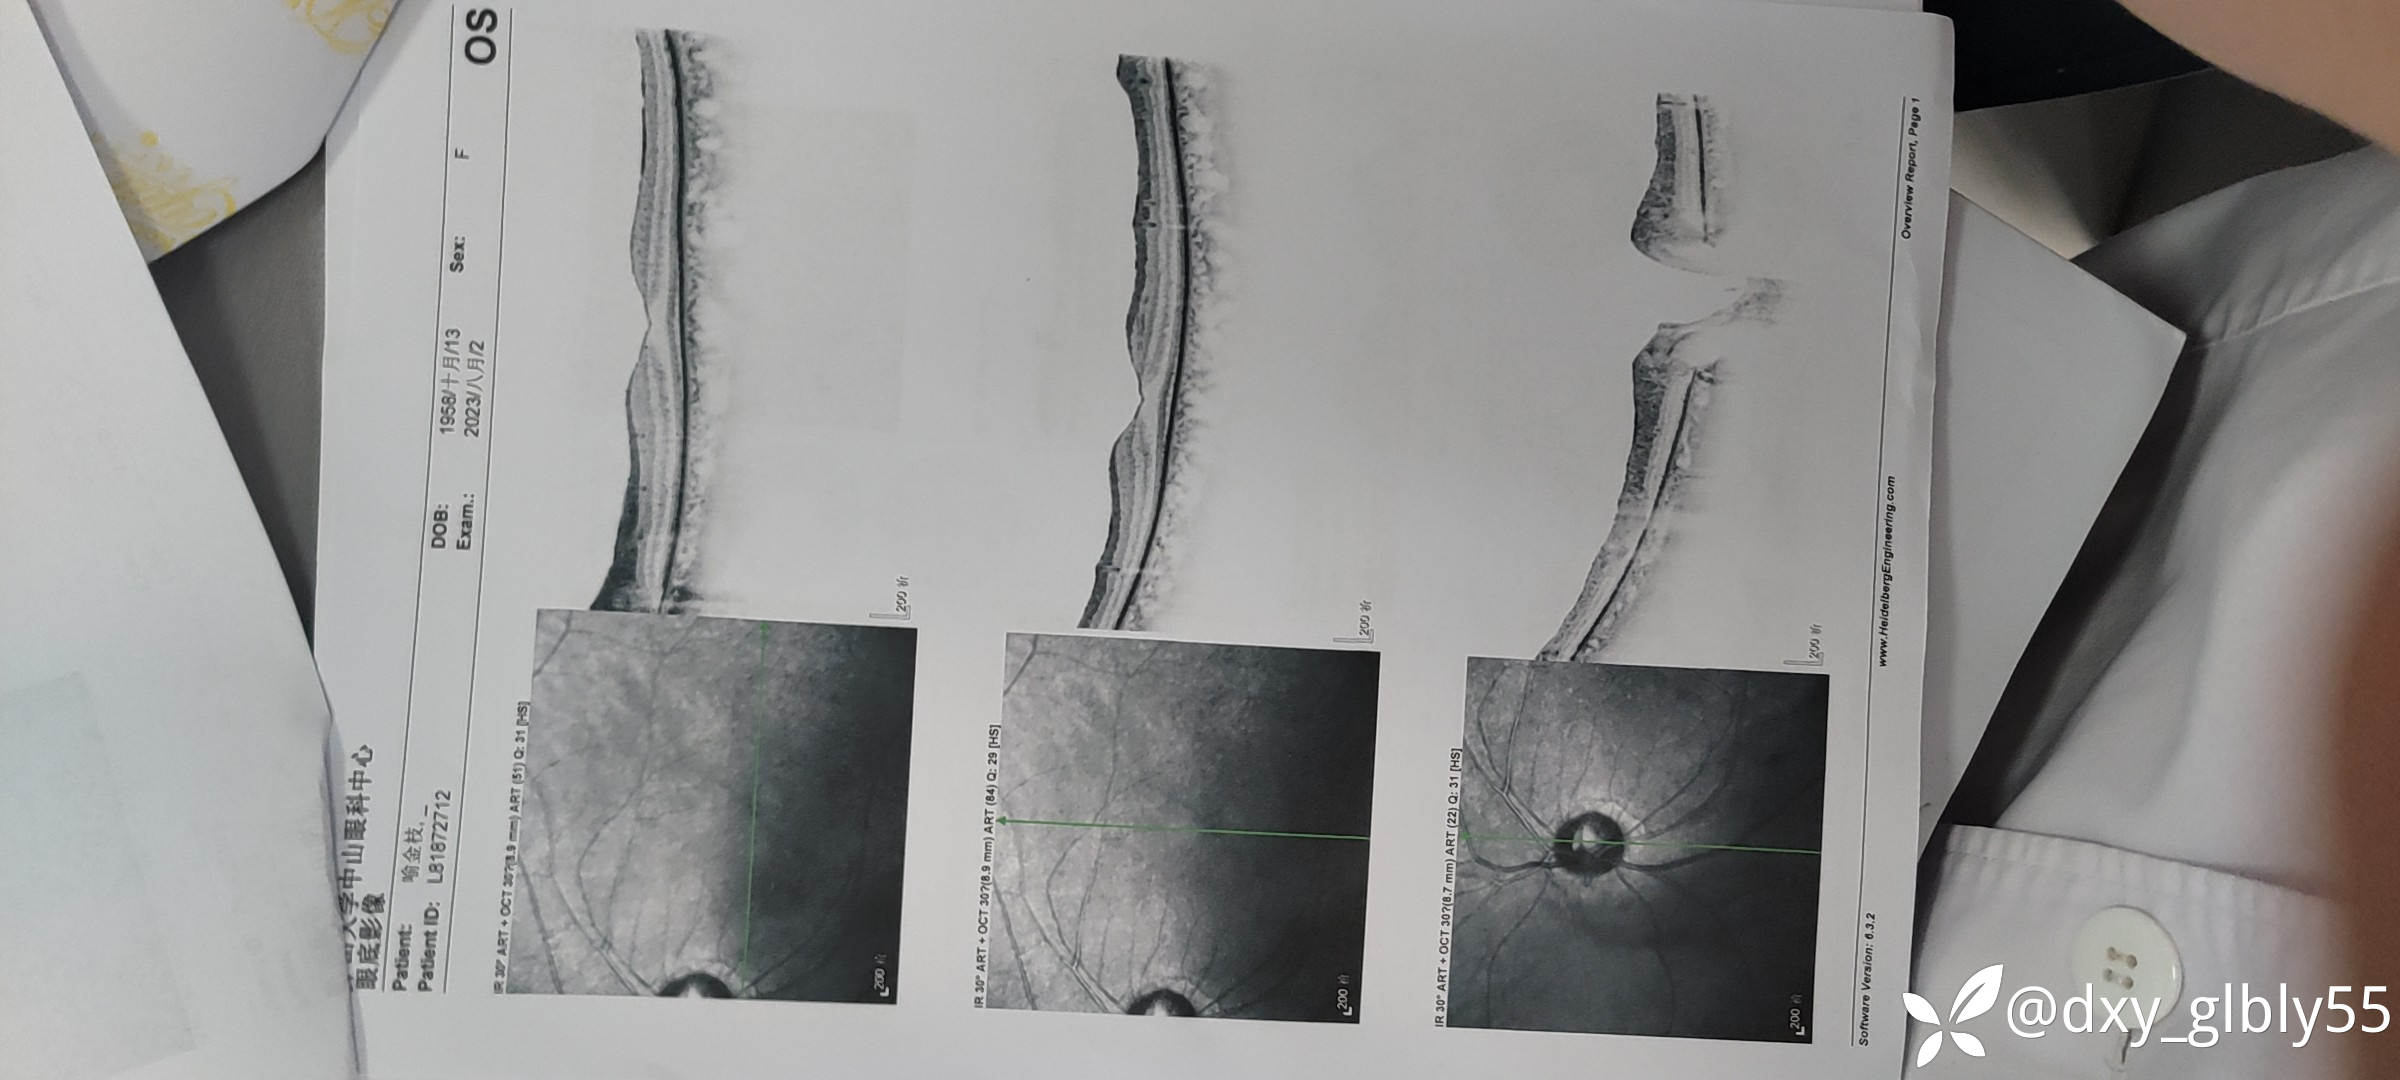

这个病人做完手术后因为效果没有达到她的期待,所以后续就没有怎么跟我联系,今年年初的时候患者因为视力下降的已经比较明显了,所以再次找到我,当时给她查的视力等专科情况vod:指数/1m vos:指数20/cm

就诊纪录以及一些有价值的特检结果我放在下面,除了电生理检查有异常在其他的特检没有表现明显的异常

一些特检结果我放在下面,请各位老师帮忙看一下,这个病人看了很多地方,很是苦恼